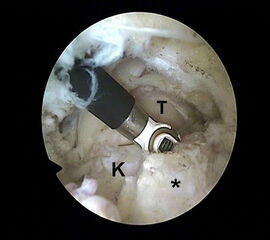

Abbildung Nr. 11-13

Das Os trigonum wird aus dem Weichteilgewebe gelöst und anschließend mit einer Fasszange entfernt. Bei größeren Knochenfragmenten muss ggf. das mediale Arthroskopieportal um wenige Millimeter verlängert werden, um die Extraktion zu ermöglichen. Nach Resektion des Os trigonum ist die posteriore Facette des Subtalargelenks erkennbar (rechte Seite, PF=posteriore Facette, FHL=Flexor hallucis longus-Sehne, T = Talus, K = Kalkaneus, *=Os trigonum).